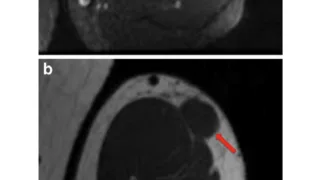

妻の頭痛7時前に起床.昨晩も炬燵で寝落ちしていました.リビングに降りて来た妻が, 「頭が痛い」と訴えました.ズキズキする頭痛とのことで, 自宅にあった頭痛薬マクサルトを内服するように促しました.妻は, 脳腫瘍の既往があり, 頭痛を訴えられる...

手術日+728日目 2026/2/25(水)(筋肉内神経鞘腫)